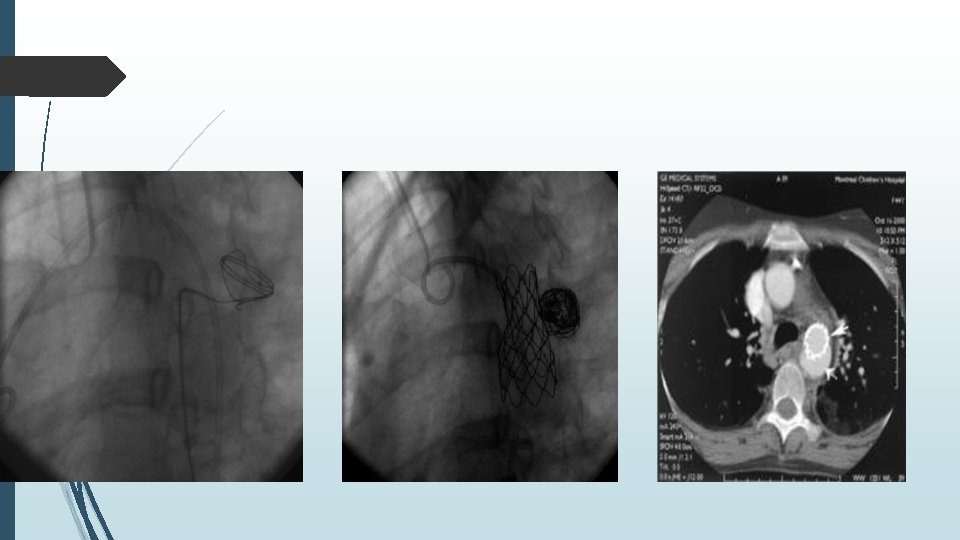

MATERIEL ET METHODES CP-stent

Procédure de traitement des coarctations Imagerie pré-thérapeutique par TDM : Confirmation du diagnostic Mesure des diamètres aortiques : coarctation, aorte horizontale et aorte descendante à son passage diaphragmatique : choix du stent. Distance coarctation/artère sous-clavière gauche Axes ilio-fémoraux

Sous anesthésie générale � Abord fémoral artériel avec utilisation de dispositif occlusif de type Perclose � Temps diagnostique : aortographie et mesure des pressions avec confirmation d’un gradient de pression entre l’aorte horizontale et l’aorte descendante � Guide rigide � Mise en place d’une gaine de 12 à 14 F

Le CP-stent est placé en aval de l’artère sousclavière gauche � Inflation du BIB-ballon permettant expansion du CP-stent � Contrôle de la disparition du gradient de pression � Geste réalisé sous héparinothérapie et antibioprophylaxie, puis mise sous antiaggrégant plaquettaire 6 mois

Surveillance Clinique : � Pression artérielle � Pouls fémoraux et distaux � Imagerie : � Échocardiographie : mesure des gradients trans-isthmiques moyens et maximum � Doppler artériel ilio-fémoral : en cas de diminution des pouls périphériques � Radiographie thoracique : position du stent � Imagerie en coupes : � TDM à H 48 � TDM à M 6 � TDM tous les ans pendant 5 ans